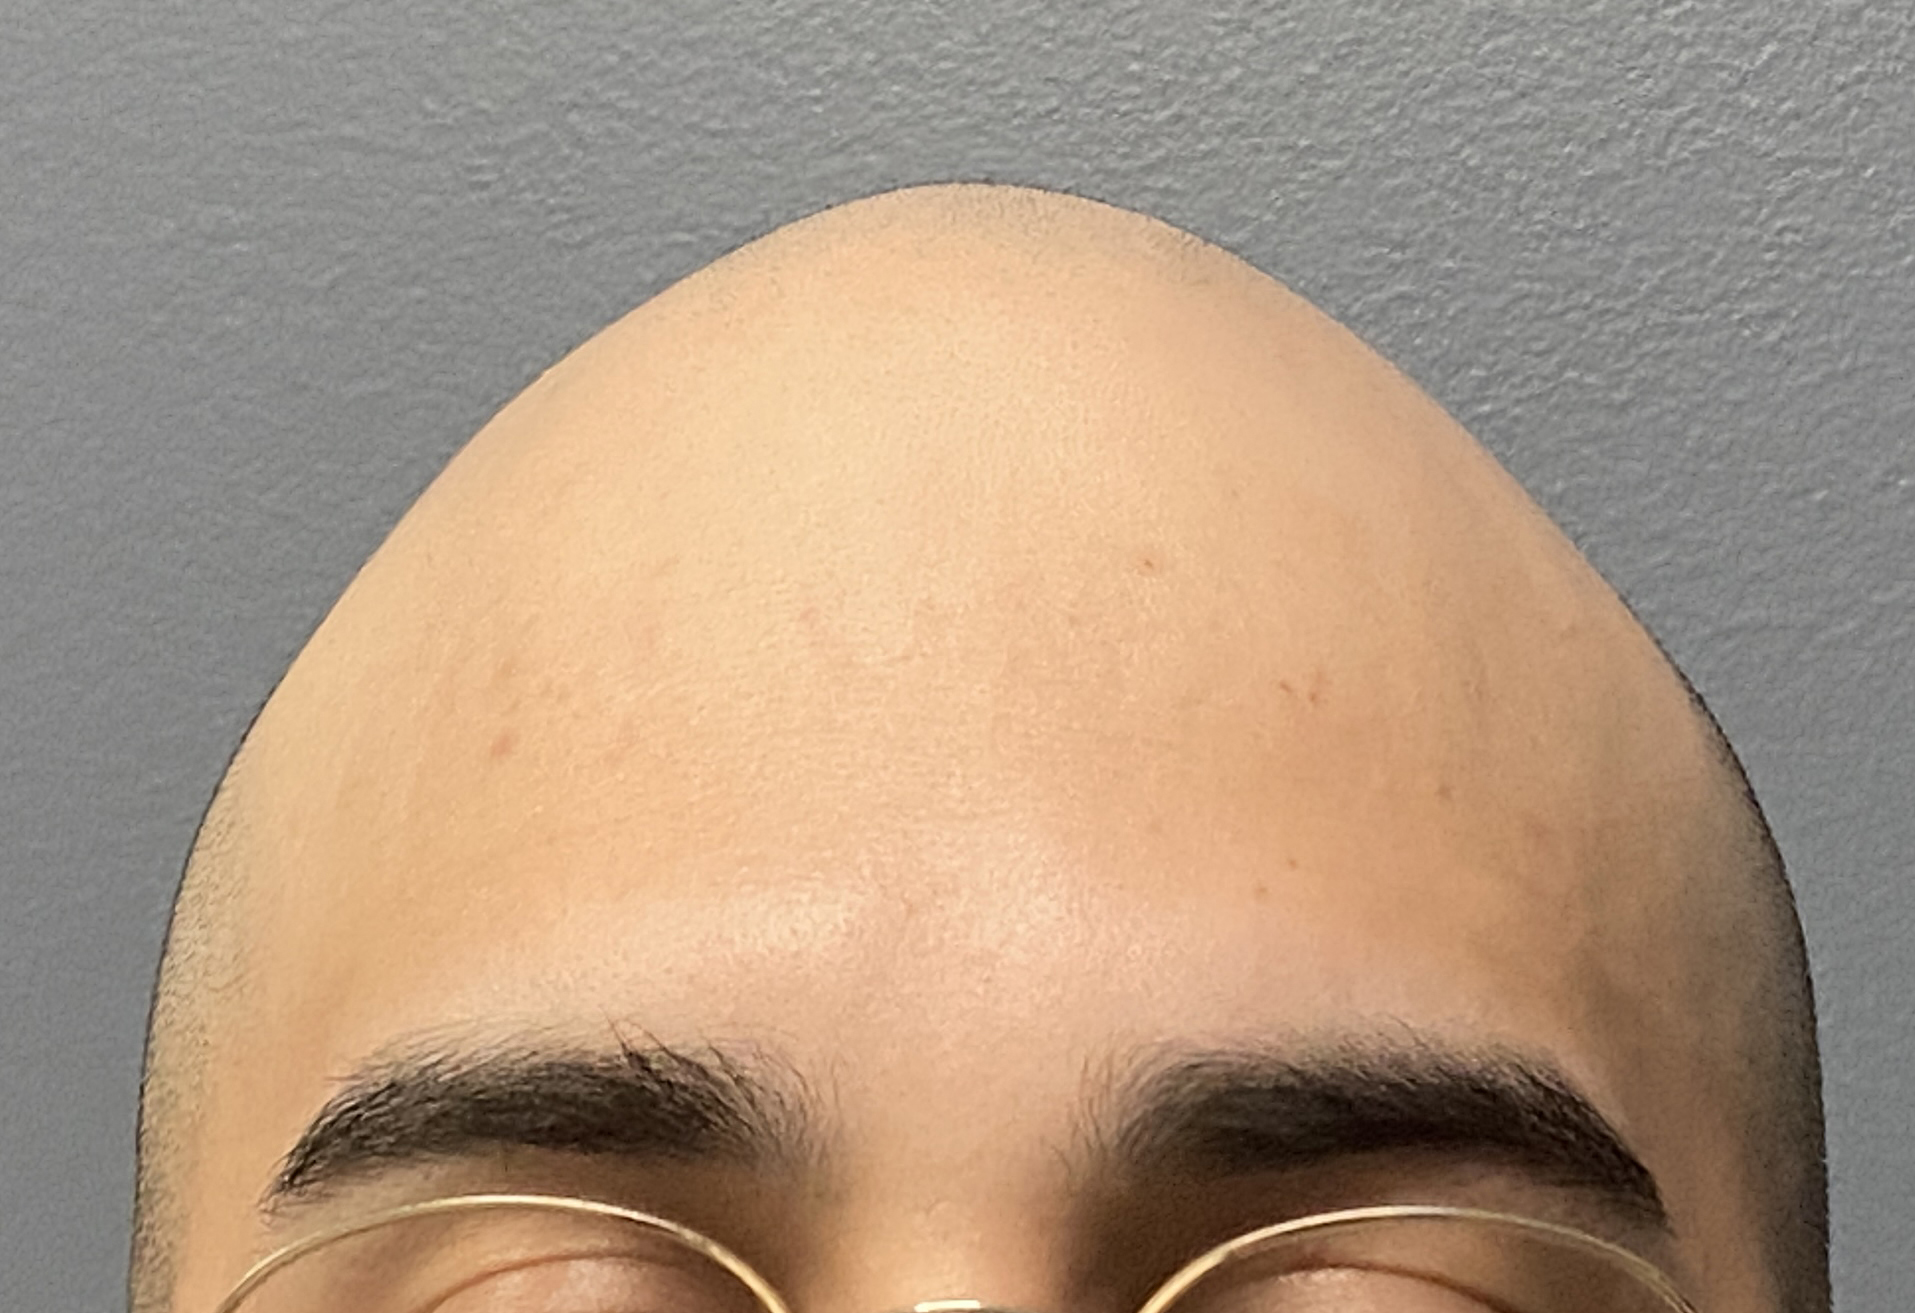

Desire for reshaping of an asymmetric flat back of the head in a shaved head male.

A combined back of the head reshaping procedure was done with a custom skull implant, sagittal ridge reduction and a right temporal muscle reduction.

Desire for reshaping of an asymmetric flat back of the head in a shaved head male.

A combined back of the head reshaping procedure was done with a custom skull implant, sagittal ridge reduction and a right temporal muscle reduction.